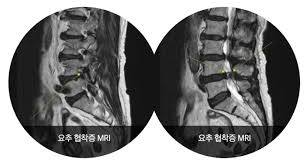

허리협착증은 척추 속 신경이 지나가는 통로인 '척추관'이 좁아지면서, 신경을 눌러 통증이나 저림 등의 증상을 유발하는 질환입니다.

- 요추관협착증은 주로 허리 부분(L3~L5)의 협착으로 인해 발생합니다.